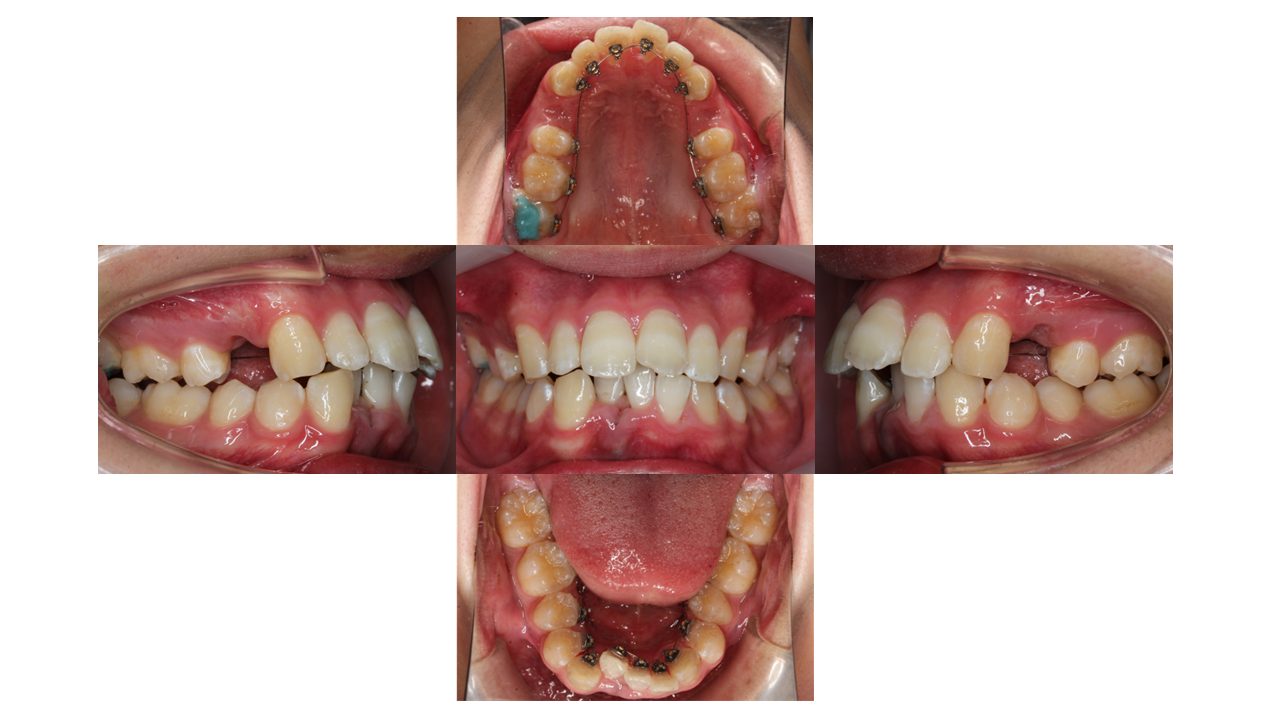

装置装着時の口腔内の状態です。

上顎左右4番目の箇所を抜歯し、裏側矯正(リンガル矯正)で歯を動かしていきます。

現在の歯並びだと、下の歯が上の歯の装置にぶつかってしまう状態のため、上の奥歯にバイトアップという青い材料をつけています。